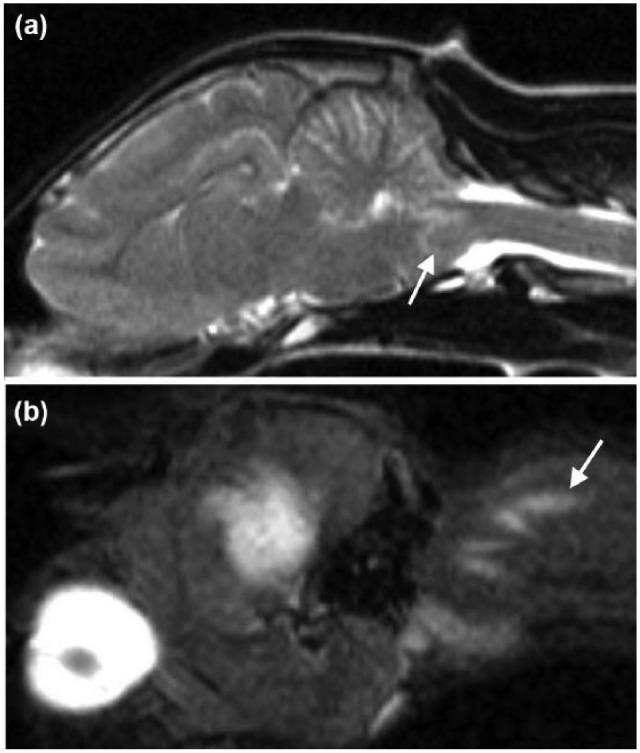

A 6-month-old female domestic shorthair cat was presented with acute onset non-ambulatory right hemiparesis and horizontal nystagmus following an injection attempt in the neck, during which the cat did not cooperate. Magnetic resonance imaging (MRI) revealed a well-defined intra-axial lesion on the right side of the myelencephalon. The lesion was T2-weighted hypointense and T1-weighted hypointense to isointense to grey matter, non-contrast enhancing, with perilesional oedema and signal void on T2*-weighted images. A linear hyperintense lesion in the muscles of the right dorsolateral aspect of the neck on short tau inversion recovery images was also observed. These MRI findings were consistent with iatrogenic brainstem haemorrhage and a muscle needle tract. The cat made a good recovery with just mild residual neurological deficits 6 weeks after the injury.

一只6个月大的雌性家养短毛猫,在颈部注射时未配合,之后出现急性发作的右半身轻瘫且不能行走以及水平性眼球震颤。磁共振成像(MRI)显示延髓右侧有一个边界清晰的轴内病变。该病变在T2加权像上呈低信号,在T1加权像上相对于灰质呈低信号至等信号,无强化,在T2*加权像上有病灶周围水肿和信号缺失。在短tau反转恢复序列图像上,还观察到颈部右背外侧肌肉有一条线性高信号病变。这些MRI表现符合医源性脑干出血和肌肉针道。该猫在受伤6周后恢复良好,仅遗留轻度神经功能缺损。